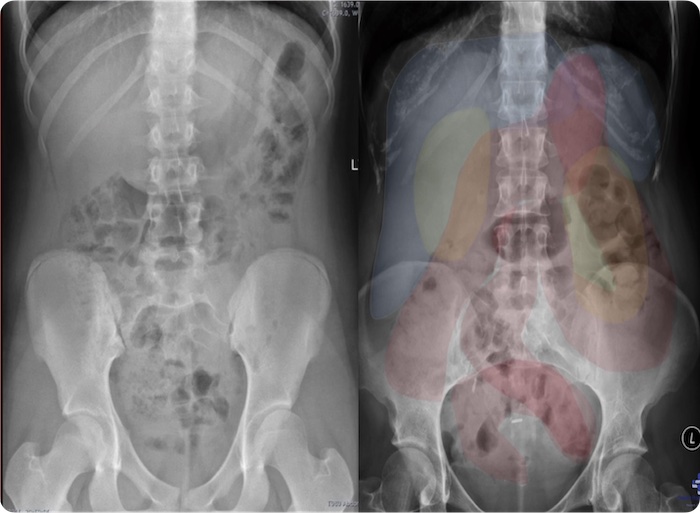

Introduction to Radiology – Chest and Abdomen

- Overview of Radiograph Interpretation

- Chest, Shoulder, Clavicle Radiographs

- Systemic Reading Process

- Abnormal Radiographs

- Radiographic Signs of Major Diseases

CT Essentials for the Abdomen and Pelvis

- CT study types

- Identification of bleeding

- Kidney Stones

- Infarctions

- Hernias

- Bowel Obstructions

- Adrenal adenomas